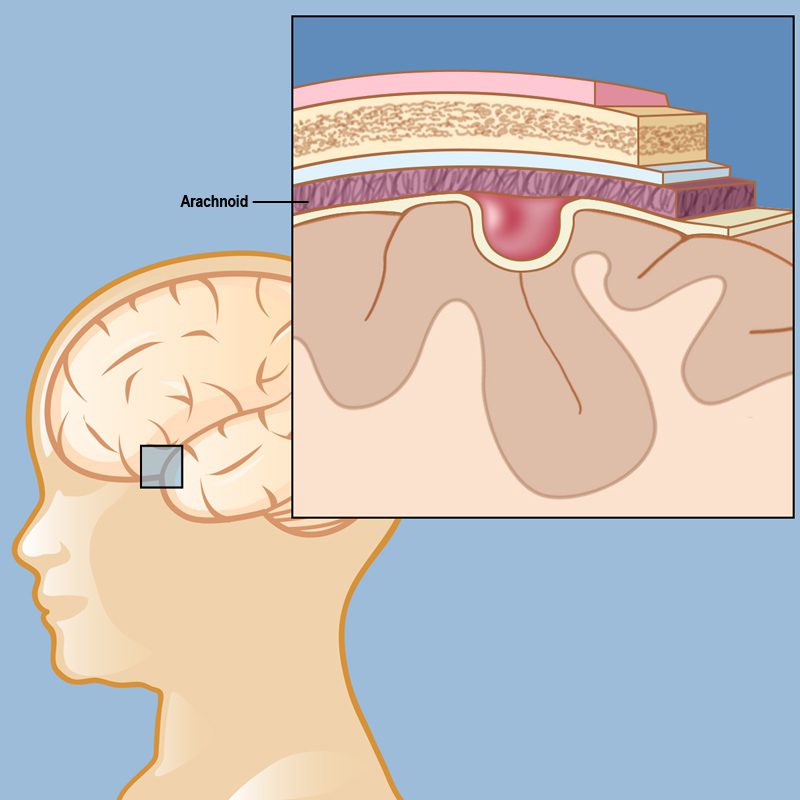

الكيس العنكبوتي عبارة عن أكياس مملوءة بالسوائل تتكون بين أوراق الغشاء العنكبوتي من الأغشية المحيطة بالدماغ والحبل الشوكي. يحتوي الدماغ على أغشية من الخارج إلى الداخل تسمى الأم الجافية والعنكبوتية والأم الحنون. على الرغم من وجود الكيسات العنكبوتية في العنكبوتية، فإنها عادة ما تتمدد إلى الداخل. المكان الأكثر شيوعًا لتواجدها هو بالقرب من الفص الصدغي للدماغ. يمكن رؤيتها أيضًا في البطين الثالث، والمنطقة فوق السرج التركي، والمخيخ، وجذع الدماغ. السبب الحقيقي لحدوثه غير معروف. نادرًا ما يتطور الكيس العنكبوتي بسبب الصدمة أو الورم أو العدوى أو جراحة الأعصاب.

الكيس العنكبوتي هو أكثر أنواع كيسات الدماغ شيوعًا ويحدث بسبب تراكم السائل النخاعي. لا تعتبر هذه الأكياس ورما دماغيا. تتشكل الأكياس العنكبوتية بين الدماغ أو النخاع الشوكي والغشاء العنكبوتي. عادة ما تكون هذه الأكياس موجودة عند الولادة ولكنها تحدث أحيانًا نتيجة إصابة في الرأس أو جراحة أو التهاب في الرأس وما إلى ذلك.